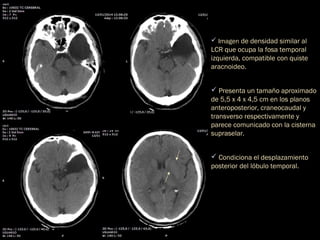

 Imagen de densidad similar al

LCR que ocupa la fosa temporal

izquierda, compatible con quiste

aracnoideo.

 Presenta un tamaño aproximado

de 5,5 x 4 x 4,5 cm en los planos

anteroposterior, craneocaudal y

transverso respectivamente y

parece comunicado con la cisterna

supraselar.

 Condiciona el desplazamiento

posterior del lóbulo temporal.